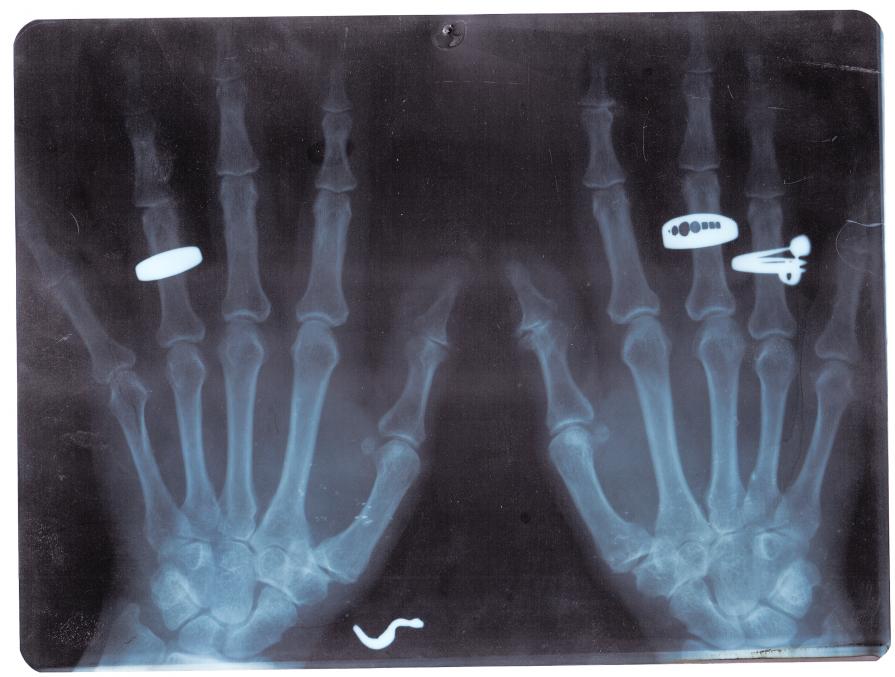

Il recupero di radiografie appartenute a un ortopedico attivo negli anni '80, permettono un'incursione attraverso il tema dell'errore, degli spazi del discorso nell'immagine e dello slittamento del senso.

La dislocazione produce delle opere simili ai rayogrammi di Man Ray o agli equivalenti di Stieglitz, continuando allo stesso tempo a parlarci della pratica vernacolare.